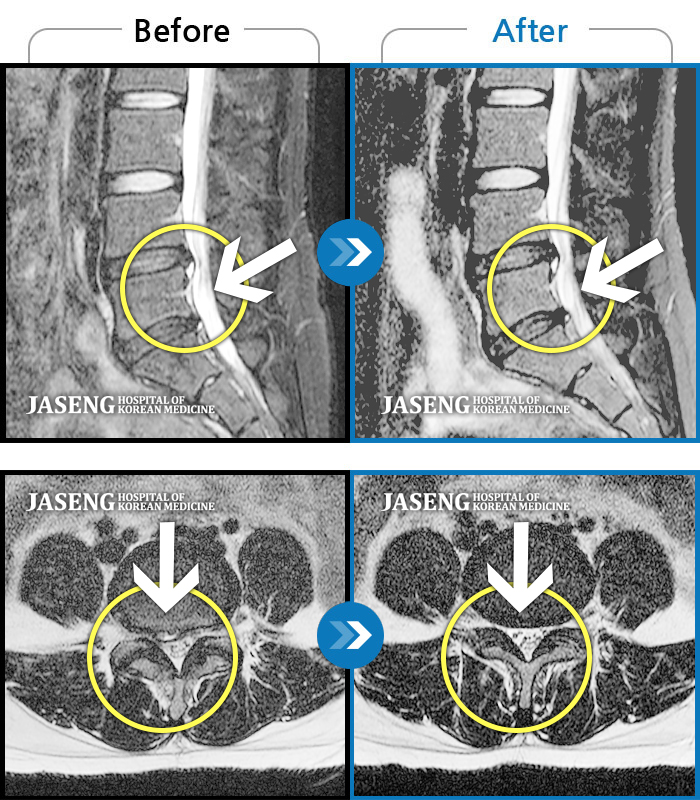

허리디스크

인천 · 강아현 원장

물건을 들다 삐끗한 후 발생한 허리 통증 및 하지 방사통, 하지 감각 저하 및 근력 저하 발생

촬영시기

2025.03.04 ~ 2025.09.10

2025.09.22

조회수 248